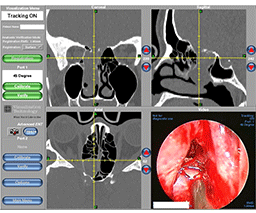

Computer Image-Guided Sinus Surgery represents a technological advance in the performance of sinus surgery using surgical navigation systems.

These devices track movement of a surgical instrument, depicting the tip of the instrument on a near three-dimentional video display of the patient's preoperative sinus CT scan.

Such information can then be used by the surgeon to confirm the exact anatomic location of the surgical instrument within the sinus cavities, particularly, its proximity to the adjacent skull base and orbit.